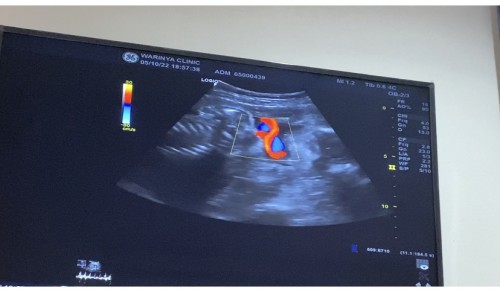

สายสะดื้อพันคอ

มีแม่ๆบ้านไหน อายุครรภ์27 วีค สายสะดื้อคอ 1 รอบบ้างค่ะ น้องกลับหัวลงแล้ว ตอนนี้น้องน้ำหนัก 1158 กรัม หมอเคร่งให้นับลูกดิ้น กลัวเด็กขาดอากาศหายใจ แอบเครียดนิดหน่อย

ไปมาวันนี้เลยค่ะ31วีคยังไม่กลับหัวเลยแต่ดิ้นเก่งสุดสายสะดือพันคอไป1รอบ หมอบอกคอยนับน้องดิ้นอย่าให้ต่ำกว่า10ครั้ง/วัน ตอนนี้ก็ยังดิ้นไม่หยุดไม่น่าจะมีอะไรน่าเป็นห่วง ที่แม่ห่วงตอนนี้คือน้องไม่กลับหัว😂